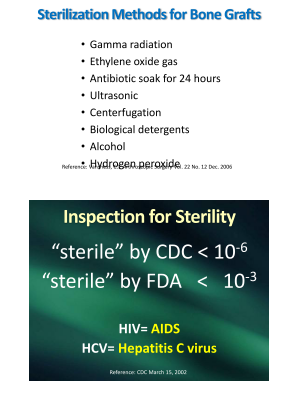

Bone grafts or your face will collapse

keep that secret under wraps

Cadaver bone in the socket

retains your beauty, so don’t knock it

Again I dream of DNA

to see if it’s really OK

Are those bone grafts really sterile

if they’re not, you’re in peril

They search for hepatitis, then for AIDS

like kids in a bacterial arcade

There are many ways to check sterility

though looking like a lesson in futility

For the lethal bacteria are left behind

obviously for the mortician to find

Grafts should be considered like transplants

not just inserted without a glance